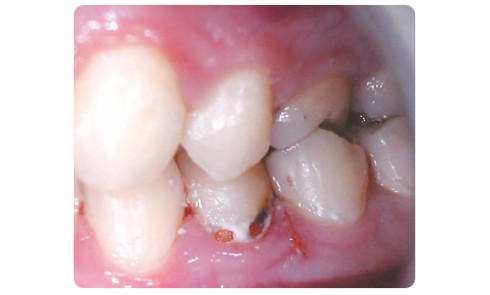

Le concept d’intervention minimale (IM) en dentisterie englobe l’ensemble des mesures préventives et interceptives à mettre en œuvre pour enrayer...